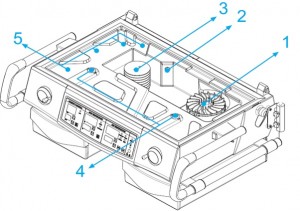

اجزای دستگاه:

۱٫دمای درون انکوباتور توسط یک المنت گرمایی(هیتر) که در زیر تشک قرار دارد افزایش پیدا می کند. این هیتر ها مقاومتی هستند.

۲٫در نزدیک هیتر، موتوری برای چرخاندن فن تعبیه شده تا هوای تازه را از فیلتر(صافی) گرفته و آن را برای گرم نمودن هوا به پشت هیتر هدایت نماید. که در شکل زیر این فن دیده می شود.در انکوباتورهای جدید فنها مجهز به سنسور القایی(اثرهال) جهت تشخیص چرخش صحیح فن می باشند. در صورتیکه این سنسور حرکت فن را حس نکند دستگاه مانع گرم شدن فن شده و آلارم خرابی دستگاه فعال می شود.

گردش مداوم این فن، هوا را مکیده، وهوا پس از عبور از فیلتر و تصویه آن به داخل می کشد. فیلتر باید هرازگاهی بررسی شود و در صورت کثیف بودن تعویض شود..

۳٫همچنین تمامی انکوباتورها جدا از دماسنج هایی که دمای محفظه را نشان می دهند دارای سنسورهایی برای تشخیص دمای هوا بوده که موجب قطع و وصل ولتاژ هیتر و در نتیجه تنظیم دمای داخل انکوباتور در یک مقدار ثابت می گردد.

هوای مکیده شده پس از مخلوط شدن با هوای داخلی در اثر برخورد با المنت حرارتی گرم می شود(میزان گرما دهی المنت توسط اپراتور قابل تنظیم است). به دلیل مثبت بودن فشار داخل محفظه، از ورود ذرات خارجی به داخل جلوگیری می شود.

۴٫درصورت نیاز به رطوبت با فعال کردن قسمت مربوط به رطوبت محفظه و تنظیم آن به میزان دلخواه، رطوبت مناسب هوای داخل محفظه تامین می شود.

هوا از طریق شکاف های موجود در داخل فضای بالای تشک داخل انکوباتور جریان پیدا می کند و به چرخش در می آید. دمای هوای موجود به وسیله سنسورهای دمایی داخل دستگاه مانیتور شده و با فرمان کنترلی که به هیتر می رسد، تنظیم می گردد..